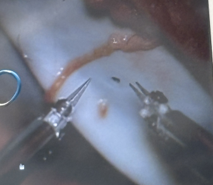

Adult female underwent nipple-sparing mastectomy with bilateral IBR using implants and ADM. Robotic-assisted nerve coaptation performed using Symani with 11-0 suture on ~0.4mm nerves. Autograft from 4th/5th medial nerve used. Sensation expected to return in 3 months.